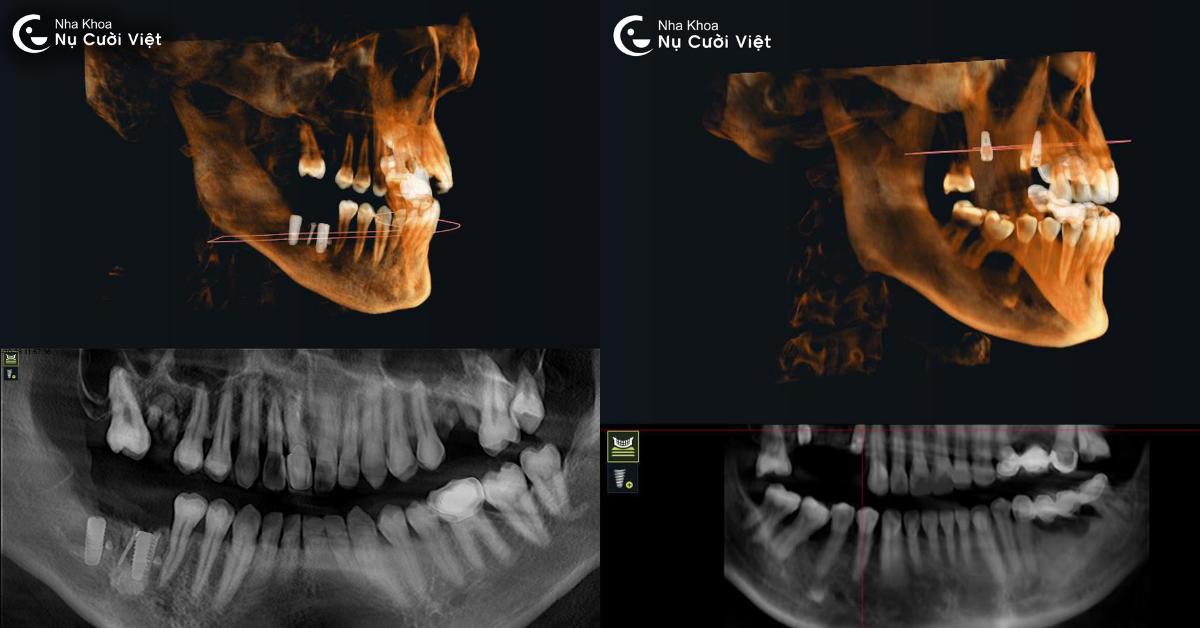

Trồng răng Implant được xem là giải pháp phục hồi răng mất toàn diện và hiện đại nhất hiện nay. Tuy nhiên, để ca cấy ghép đạt độ chính xác và hiệu quả tối đa, bác sĩ cần nắm rõ từng chi tiết về cấu trúc xương hàm, mô mềm và các vùng giải phẫu lân cận.

Chính vì vậy, chụp phim ConeBeam CT 3D là bước đầu tiên và không thể thiếu trong quá trình trồng răng Implant. Công nghệ này không chỉ giúp bác sĩ quan sát toàn diện vùng hàm mặt mà còn tạo nền tảng dữ liệu 3D chính xác, phục vụ cho việc lập kế hoạch điều trị an toàn, cá nhân hóa cho từng bệnh nhân.

Kỹ thuật này sử dụng tia X hình nón để quét toàn bộ cấu trúc vùng hàm mặt và răng trong một lần chụp duy nhất. So với phim X-quang thông thường chỉ cho hình ảnh hai chiều (2D), ConeBeam CT cung cấp góc nhìn toàn cảnh ba chiều (3D) có độ phân giải cao, thể hiện chi tiết từng lát cắt của xương, mô mềm, ống thần kinh và xoang hàm. Khi thực hiện chụp, đầu máy sẽ xoay 360 độ quanh vùng hàm mặt trong vài giây để thu thập dữ liệu. Hệ thống cảm biến đặc biệt sẽ ghi lại hàng trăm lớp cắt siêu mỏng của vùng cần khảo sát.

Chỉ với một lần chụp duy nhất, bác sĩ có thể quan sát hàng triệu góc nhìn, từ trên xuống, từ dưới lên, mặt bên, mặt nghiêng… Từ đó dễ dàng phát hiện các vấn đề tiềm ẩn như tiêu xương, viêm quanh chân răng cũ, khoảng cách đến dây thần kinh, độ sâu xoang hàm… giúp quá trình lập kế hoạch trồng Implant trở nên chính xác và cá nhân hóa cho từng khách hàng.

Cone Beam CT tạo ra hình ảnh 3D chi tiết giúp đánh giá chính xác cấu trúc xương, tình trạng mô mềm